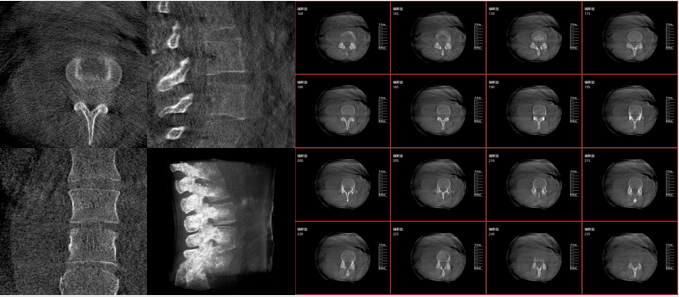

從下圖中可以看到二維影像能夠提供目標區域在某一個平面的重疊影像,雖然因為人體不同組織的密度差異,使得圖像具有較為豐富的信息量,但組織間的相互重疊還是會出現,諸如空間位置等眾多信息在影像中遺失或不可辨認的情況,影響了醫生對信息的收集與應用。

術中二維影像

而三維影像的MPR圖像組可以通過不同平面的切分,使成像區內更豐富的信息得以呈現。尤其是二維影像無法涉及的橫斷面,提供了另一個空間維度的信息量。

術中三維C臂影像